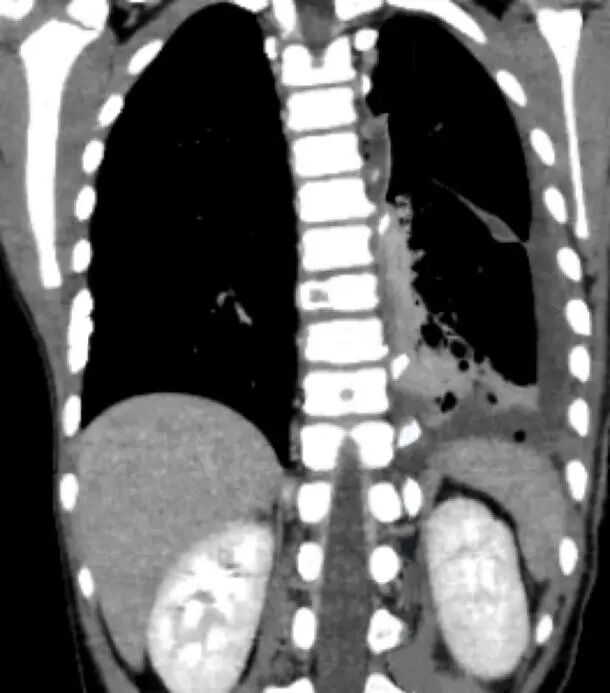

今年7月,来自新乡的浩浩(化名)突然出现间断性下肢疼痛,没过几天,右侧肋骨也开始疼。本以为只是生长痛,但一张详细的胸部CT检查报告,却让全家陷入了绝望——浩浩的胸腔里长了一个巨大的肿瘤。

进一步检查后,浩浩被确诊为纵隔神经母细胞瘤。更糟糕的是,癌细胞已发生多处转移:骨、骨髓、肝、肺。

3个月后,CT复查传来好消息:肿瘤明显缩小!

肿瘤位置极其凶险。肿瘤仍有约13厘米长,像一块“狗皮膏药”紧紧贴在孩子的脊柱旁,从胸腔顶部一直延伸到腰部,并且紧贴着人体最粗大的降主动脉。手术中稍有不慎,就可能引发致命性大出血。

术前